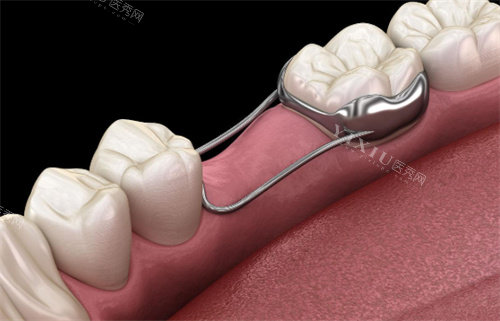

美学修复:包括全瓷牙、瓷贴面、嵌体等高美学要求的修复治疗,满足患者对美观和功能的双重需求。

王玉洁医生:全科口腔医生,精通口内治疗、儿童牙科、修复治疗等领域,在嵌体修复、根管治疗、全瓷牙修复和智齿拔除等方面技术娴熟。

美学修复:全瓷冠单颗约2000-4000元;瓷贴面单颗约2500-4500元;嵌体修复单颗约1500-3000元。